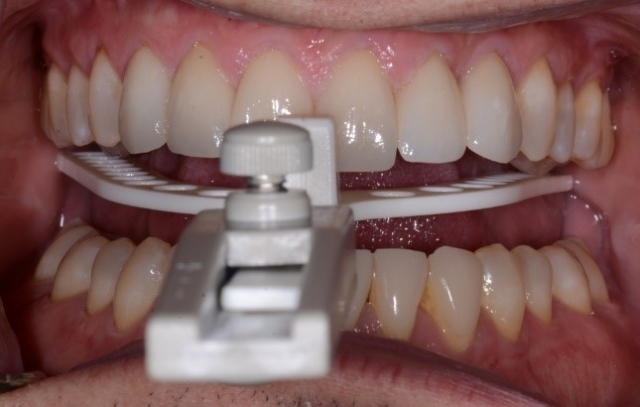

For instance, when taking a bite record to mount models in a fully seated condylar position, a leaf gauge is one of the most predictable methods to help obtain the physiological position. And one way to hold that position while scanning the bite is to use silicone and trim off the material in the premolar area before scanning the bite, thus preventing the patient from moving while moving the camera from one side to the other (Fig. 2).

Again, makes sense, right? But would you be open to the possibility that we can just quickly and accurately scan the bite while the patient maintains adequate pressure, helping seat the condyles? (Fig. 3)